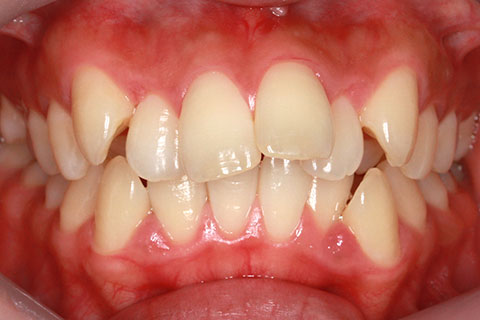

ハーフリンガル矯正4(上の歯のみ舌側矯正で治療)

治療前

治療中

治療後

- 年齢・性別

- 23歳女性

- 治療期間

- 2年0ヶ月

- 抜歯

- 上下4番抜歯

- 治療費

- 110万円

- 備考

- マルチブラケットを用いた矯正治療

- 治療内容

- 施術の副作用(リスク)

- 表側矯正と比較して、前歯のラビッティング(舌側傾斜)を起こしやすい。